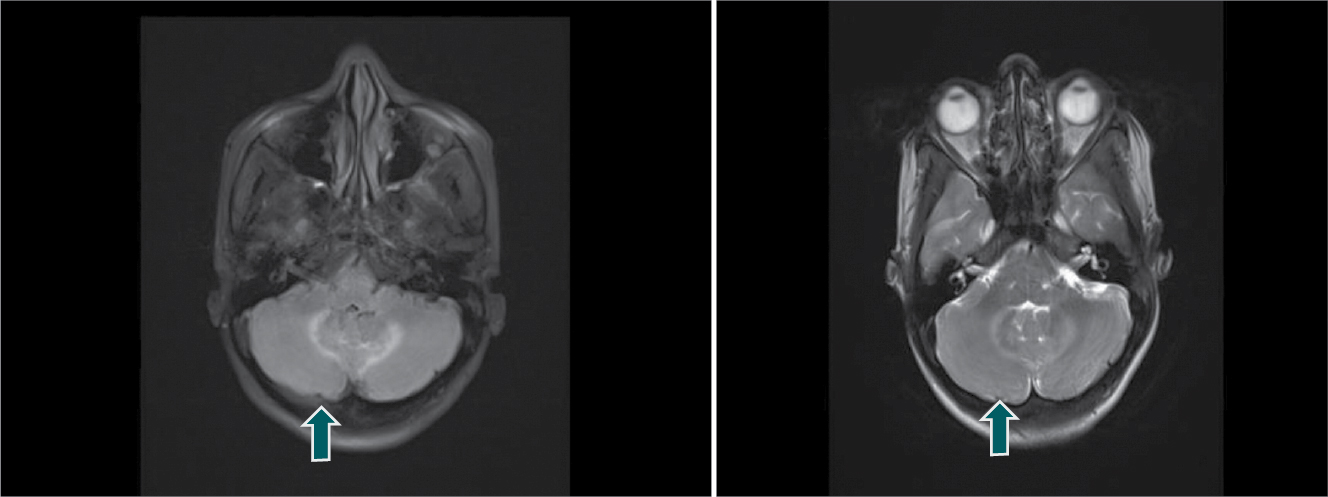

A diagnosis of scrub meningoencephalitis was made and patient was put on injection doxycycline 100 mg IV twice-daily and injection chloramphenicol 1 g IV thrice-daily along with symptomatic treatment with hydration, antipyretics and supportive care. Magnetic resonance imaging (MRI) brain (contrast-enhanced) was planned, which revealed T2/FLAIR hyperintensity in bilateral cerebellum without diffusion restriction on DWI (suggestive of cerebellitis) (Fig. 1). The patient subsequently become afebrile 3 to 4 days after treatment and started following commands. During her recovery phase, examination of the nervous system revealed dysarthric, staccato and scanning speech, head titubation, bilateral upper and lower limb in coordination in form of abnormal finger-nose and heel-shin-knee test, abnormal rapid alternating movements, wide based gait with cerebellar ataxia, truncal ataxia, nystagmus and tremors of both hands. Cranial nerve/motor/sensory examinations were within normal limits. During hospital stay, the patient was shifted to oral doxycycline and chloramphenicol. She was discharged on doxycycline and chloramphenicol for 14 days and instructed to visit Medicine OPD for follow-up.

Figure 1. Contrast-enhanced MRI brain showing bilateral cerebellar hyperintensities (arrows) on T2 FLAIR (left) and T2 images (right) suggestive of bilateral cerebellitis.

Our case showed T2/FLAIR hyperintensity involving bilateral cerebellum. Scrub typhus response to doxycycline treatment is dramatic. Our patient too improved within 3 to 4 days of starting treatment for scrub typhus. Thus, early diagnosis and treatment is crucial to reduce complication rate and also case fatality rates. The patient may have a favorable outcome with no or minimal neurological deficit.